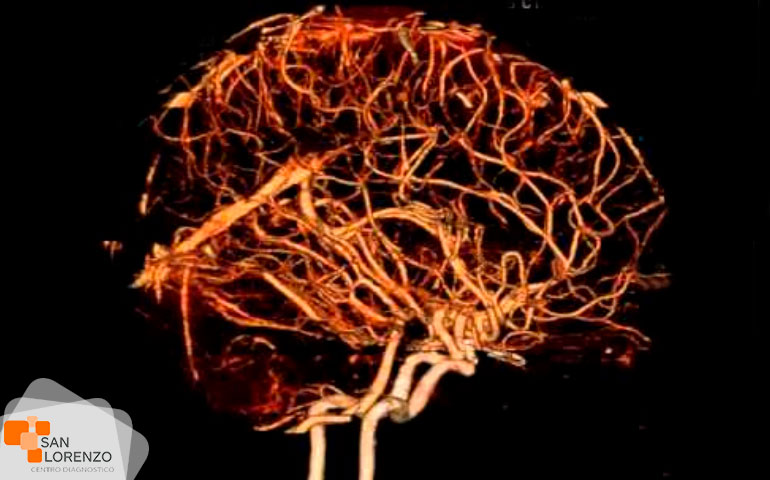

Algunos de los exámenes relacionados con medios de contraste son: Angiotac, Urotac, TAC de abdomen y pelvis, TAC de cerebro en lo que se solicite contraste, y todas aquellas Resonancias magnéticas contrastadas.

Todos los exámenes de RM, TAC que requieran contraste tal como los mencionados anteriormente: Angiotac, Urotac, TAC de abdomen y pelvis, TAC de cerebro en lo que se solicite contraste y todas aquellas Resonancias magnéticas contrastadas.